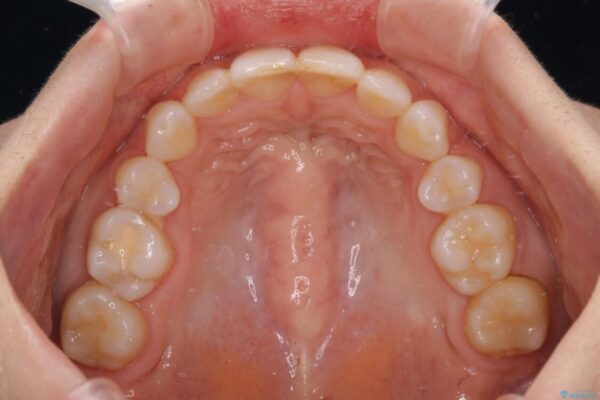

治療前

• 【モニター】出っ歯と咬み合わせを改善 ワイヤー装置の抜歯矯正 治療前画像

治療後

• 【モニター】出っ歯と咬み合わせを改善 ワイヤー装置の抜歯矯正 治療後画像